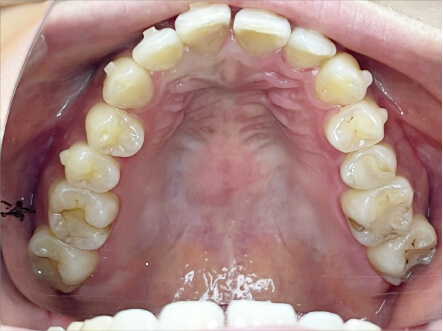

叢生の症例

19歳

女性

上の前歯が出っ歯、下の前歯がガタガタ

カウンセリング・診断結果

抜歯承諾、IPR承諾、アタッチメント承諾、ミニインプラント承諾、アレルギー有・叢生(凸凹)

治療内容・方法

全顎アライナー矯正 抜歯予定だったが抜歯リスク高いため抜歯なしでIPR量を増やす

術後の経過・現在の様子

クリアライナー

費用・治療期間

880,000円、1年5ヶ月